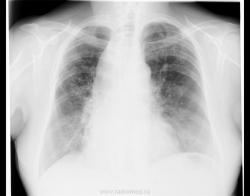

При профилактическом исследовании у женщины 75 лет выявлены изменения в легких и средостенье. Выполнена КТ. Ваше мнение, коллеги?

Ну, слева на верхушке - не провокация.

Почему провокация?! У меня что, имидж такой? о провокациях я так сразу и пишу в заголовке... Нет здесь ни провокации, ни загадки. Действительно, ахалазия кардии, пневмофиброз в легких, по-видимому метатуберкулезный. А случай мне показался интересным, потому как эта ахалазия имеет 50 лет анамнеза без лечения